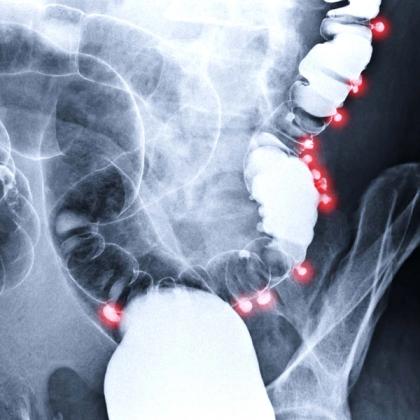

Diverticular disease is a condition characterised by the presence of small pouches, called diverticula, in the wall of the colon (large intestine). These pouches can develop when weak spots in the colon's muscular wall give way under pressure. Diverticular disease encompasses two main conditions: diverticulosis and diverticulitis. In this episode, Dr Roger Henderson takes an overview look at the symptoms and management of these as well as their prognosis and prevention.

- Diverticular disease is best defined as any clinical state caused by symptoms linked to diverticula in the large bowel. These are a herniation of mucosa through thickened colonic muscle and may be solitary or there may be hundreds present.

- Diverticulitis indicates inflammation of a diverticulum or diverticula and may be caused by infection. Other complications of diverticular disease include bleeding, infection, abscess, perforation, peritonitis, fistula formation and bowel obstruction.